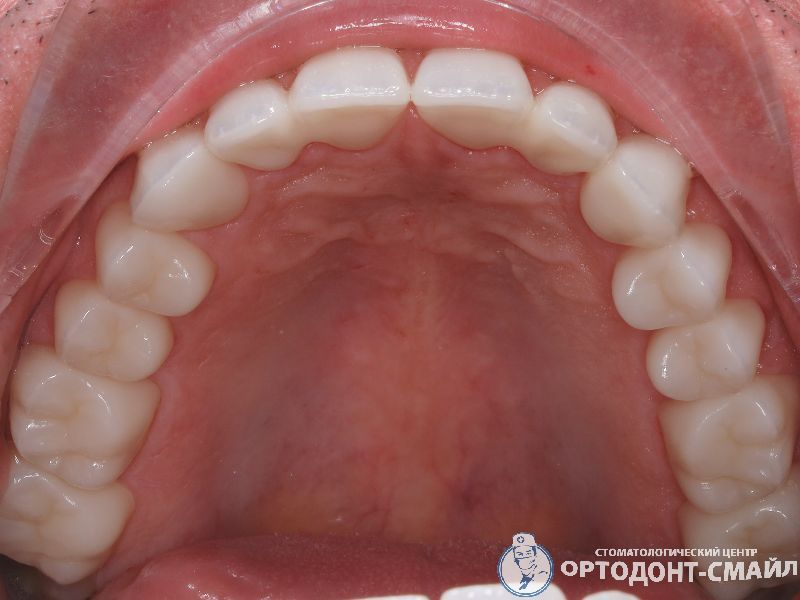

Диагноз: прямой травматический прикус, повышенная стираемость зубов.

Проведено: лечение ВНЧС, тотальная реабилитация по поднятию прикуса диоксидом циркона

верхняя челюсть